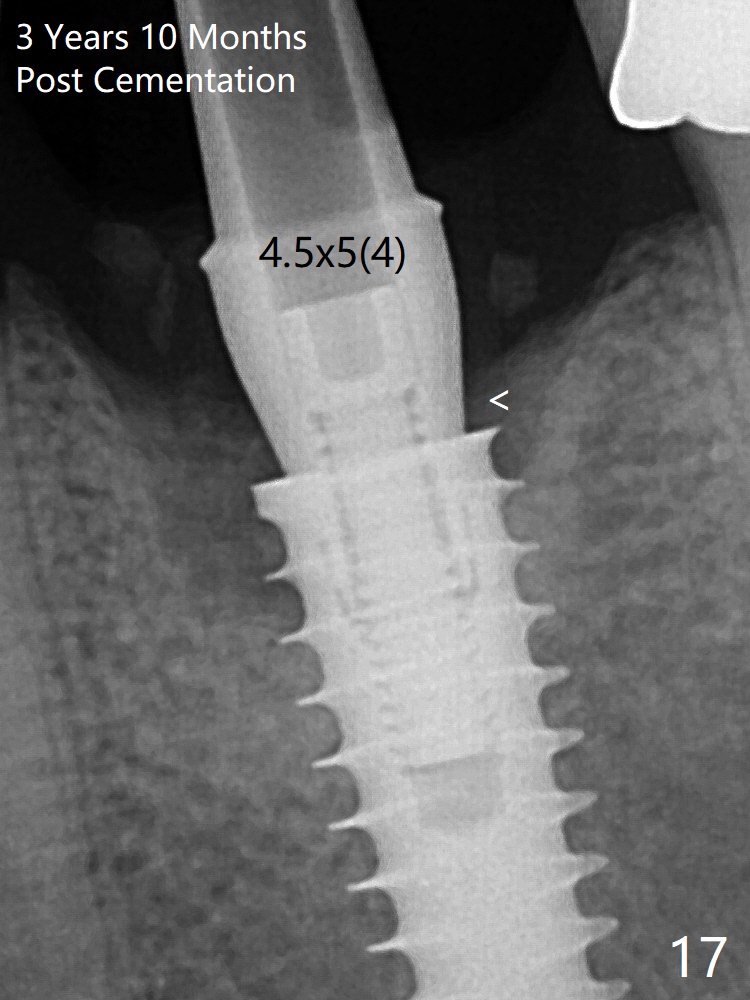

The crown/abutment is loose 3 times (3 months (Fig.14), 11 months (between Fig.14 and 15) and 2 years 3 months post cementation).  In spite of being stable 3 years 10 months post cementation, a smaller abutment is placed (Fig.17 (PA), 18 (BW)) with impression for a new crown.